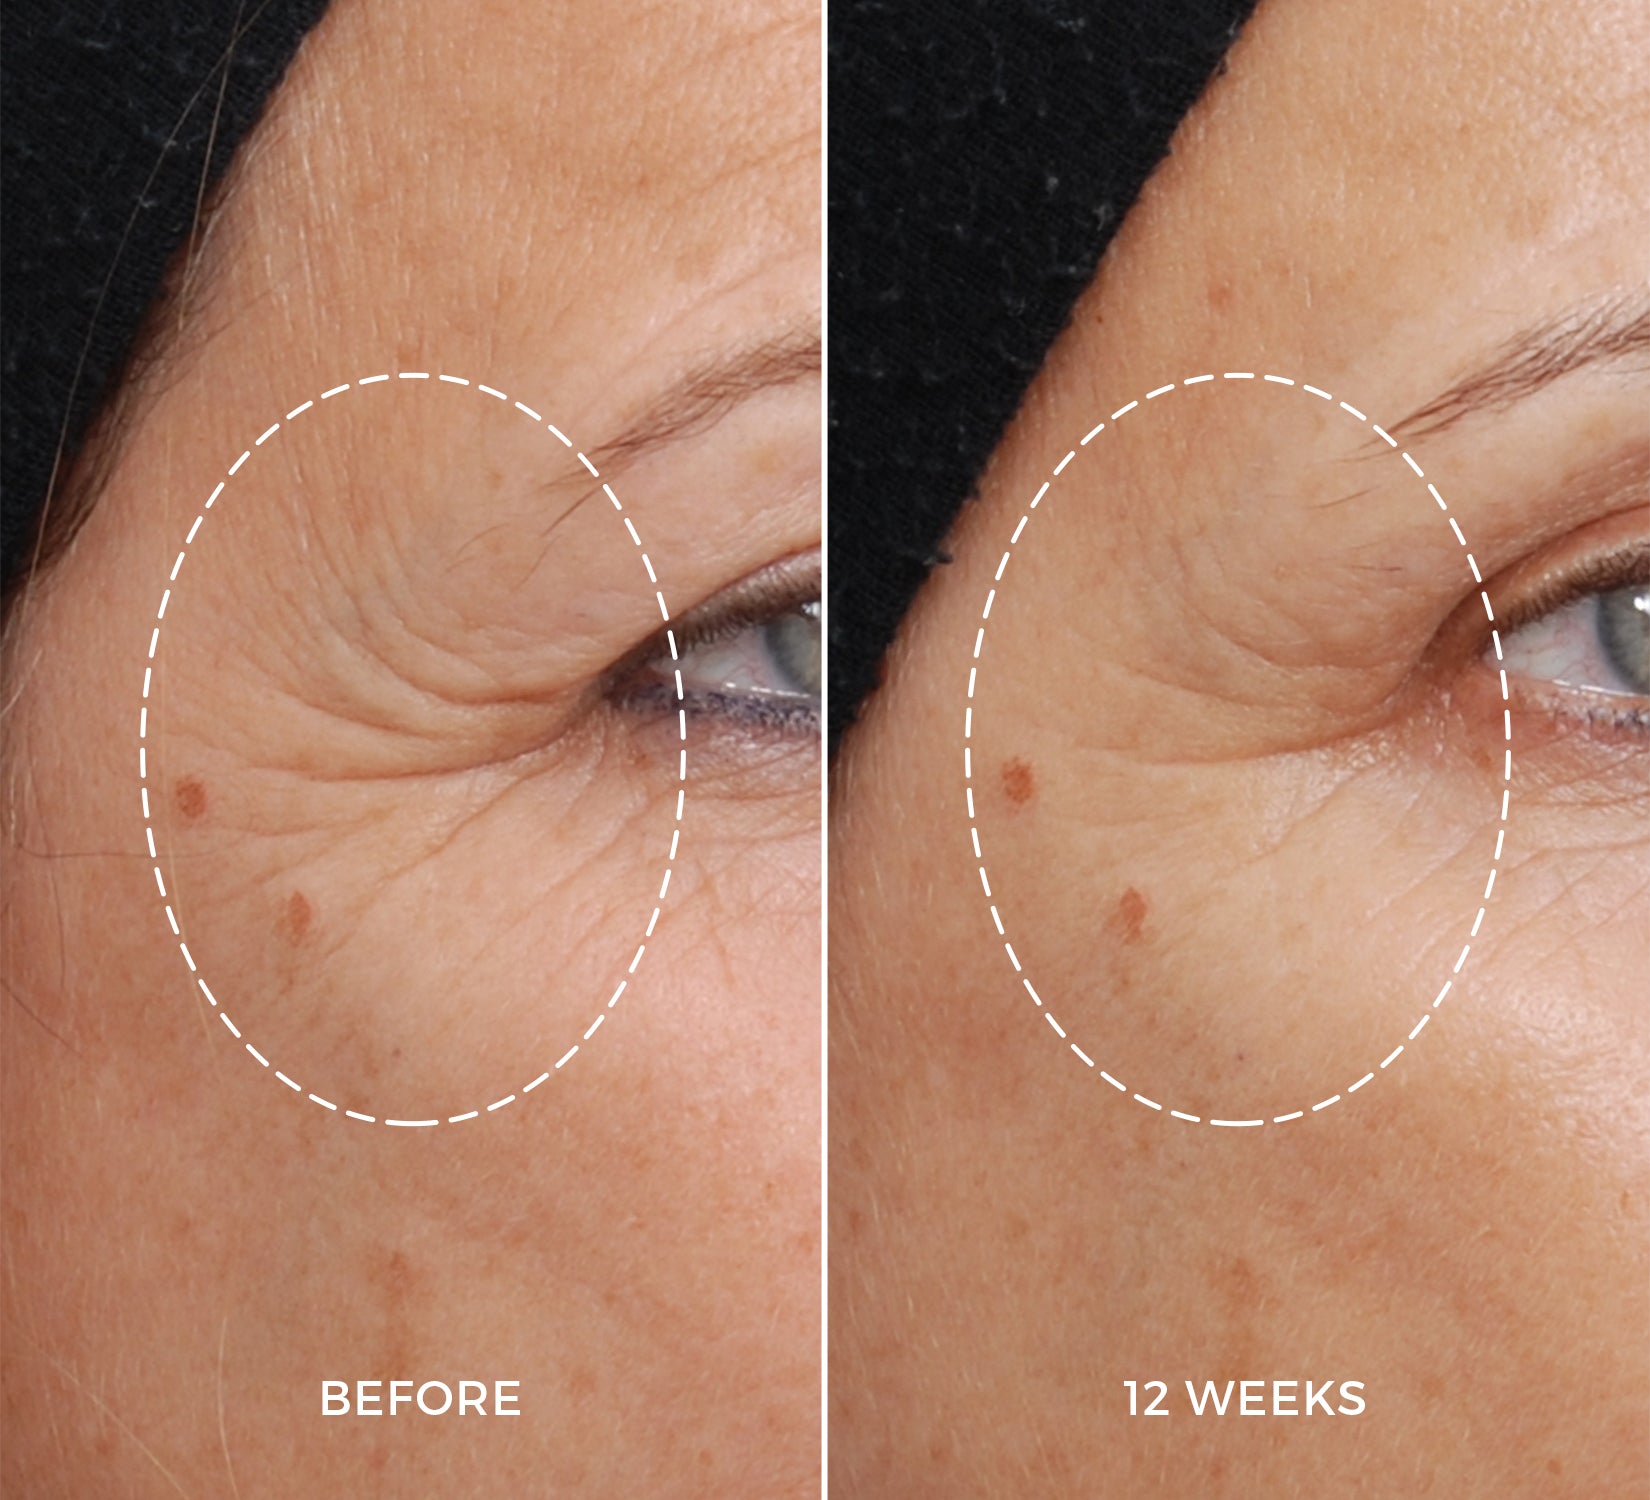

CLINICAL STUDY

Loved by your skin, backed by clinical studies.

The benefits of the NEWA device and NEWA Lift Gel on the skin’s collagen production were clinically tested on participants of various skin types aged 37 to 65. Over a period of three months, individuals who took part in the study used the NEWA combination 3 times a week for the first 4 weeks and twice a week for the remaining 8 weeks. The results were assessed by dermatologists.²

100%

of participants showed improvement in overall wrinkle appearance.

Eye Area